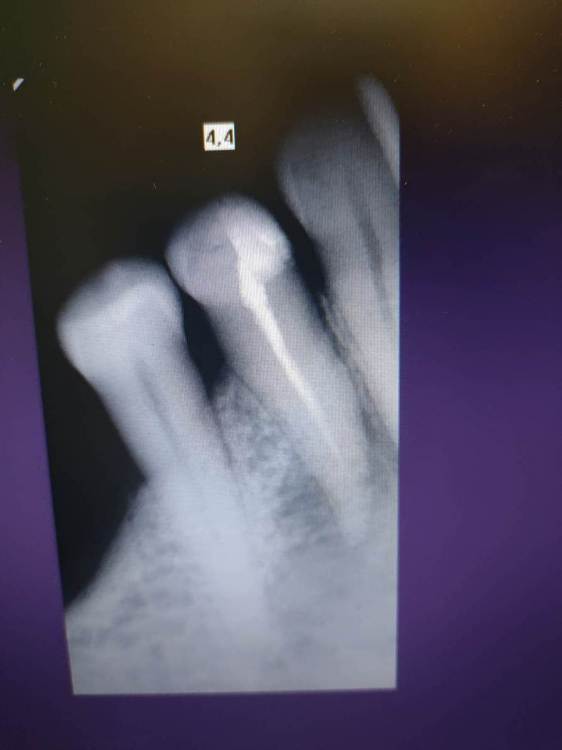

BorisJan Опубликовано 21 апреля, 2022 Поделиться Опубликовано 21 апреля, 2022 Всем доброго времени суток. На 4 нижнем обнаружили кисту, зуб лет 5 назад депульпировали. Зуб подвижен. боли при нажатии. Пациент 66 лет. Заранее извиняюсь за качество снимка. Сегодня был у стоматолога, порекомендовал удаление, либо пропить антибиотики, но говорит, что это до первого обострения. Подскажите, пожалуйста, стоит ли бороться за зуб? Ссылка на комментарий

Notherbrick Опубликовано 22 апреля, 2022 Поделиться Опубликовано 22 апреля, 2022 11 часов назад, Женька сказал: Здравствуйте. Стоит. Нужно найти доктора, который не станет советовать просто попить антибиотики, а пролечит зуб в несколько посещений и запломбирует качественно. Если вы в Москве то, думаю, найти хорошего специалиста не будет большой проблемой. Сейчас прибегут коллеги, скажут что вы не гуманный доктор и не смотрите в будущее. Проксимально кариес корня аж до середины и прогноз неблагоприятный. 1 Ссылка на комментарий